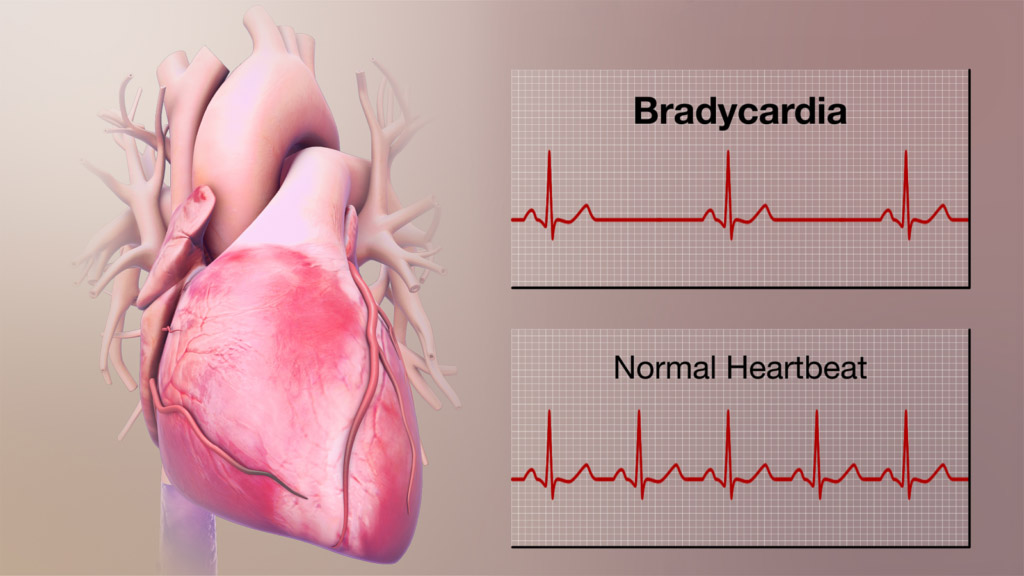

قیمت: 68٬000 تومان - دسته بندی فایل: پاورپوینتآریتمی های قلبی (ppt) 36 اسلاید کامل

فروش ویژه پاور پوینت حرفه ای آریتمی های قلبی با تخفیف استثنایی- نوع فایل : powerpoint (..ppt) ( قابل ویرایش و آماده پرینت ) تعداد اسلاید : 36 اسلاید